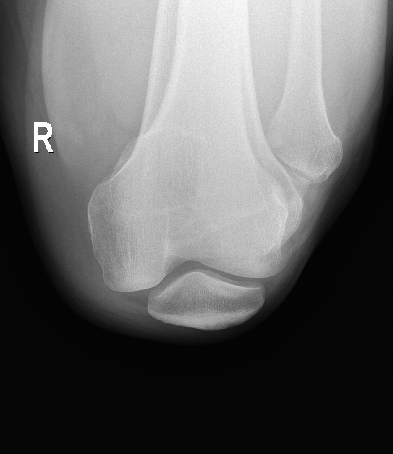

临床图像